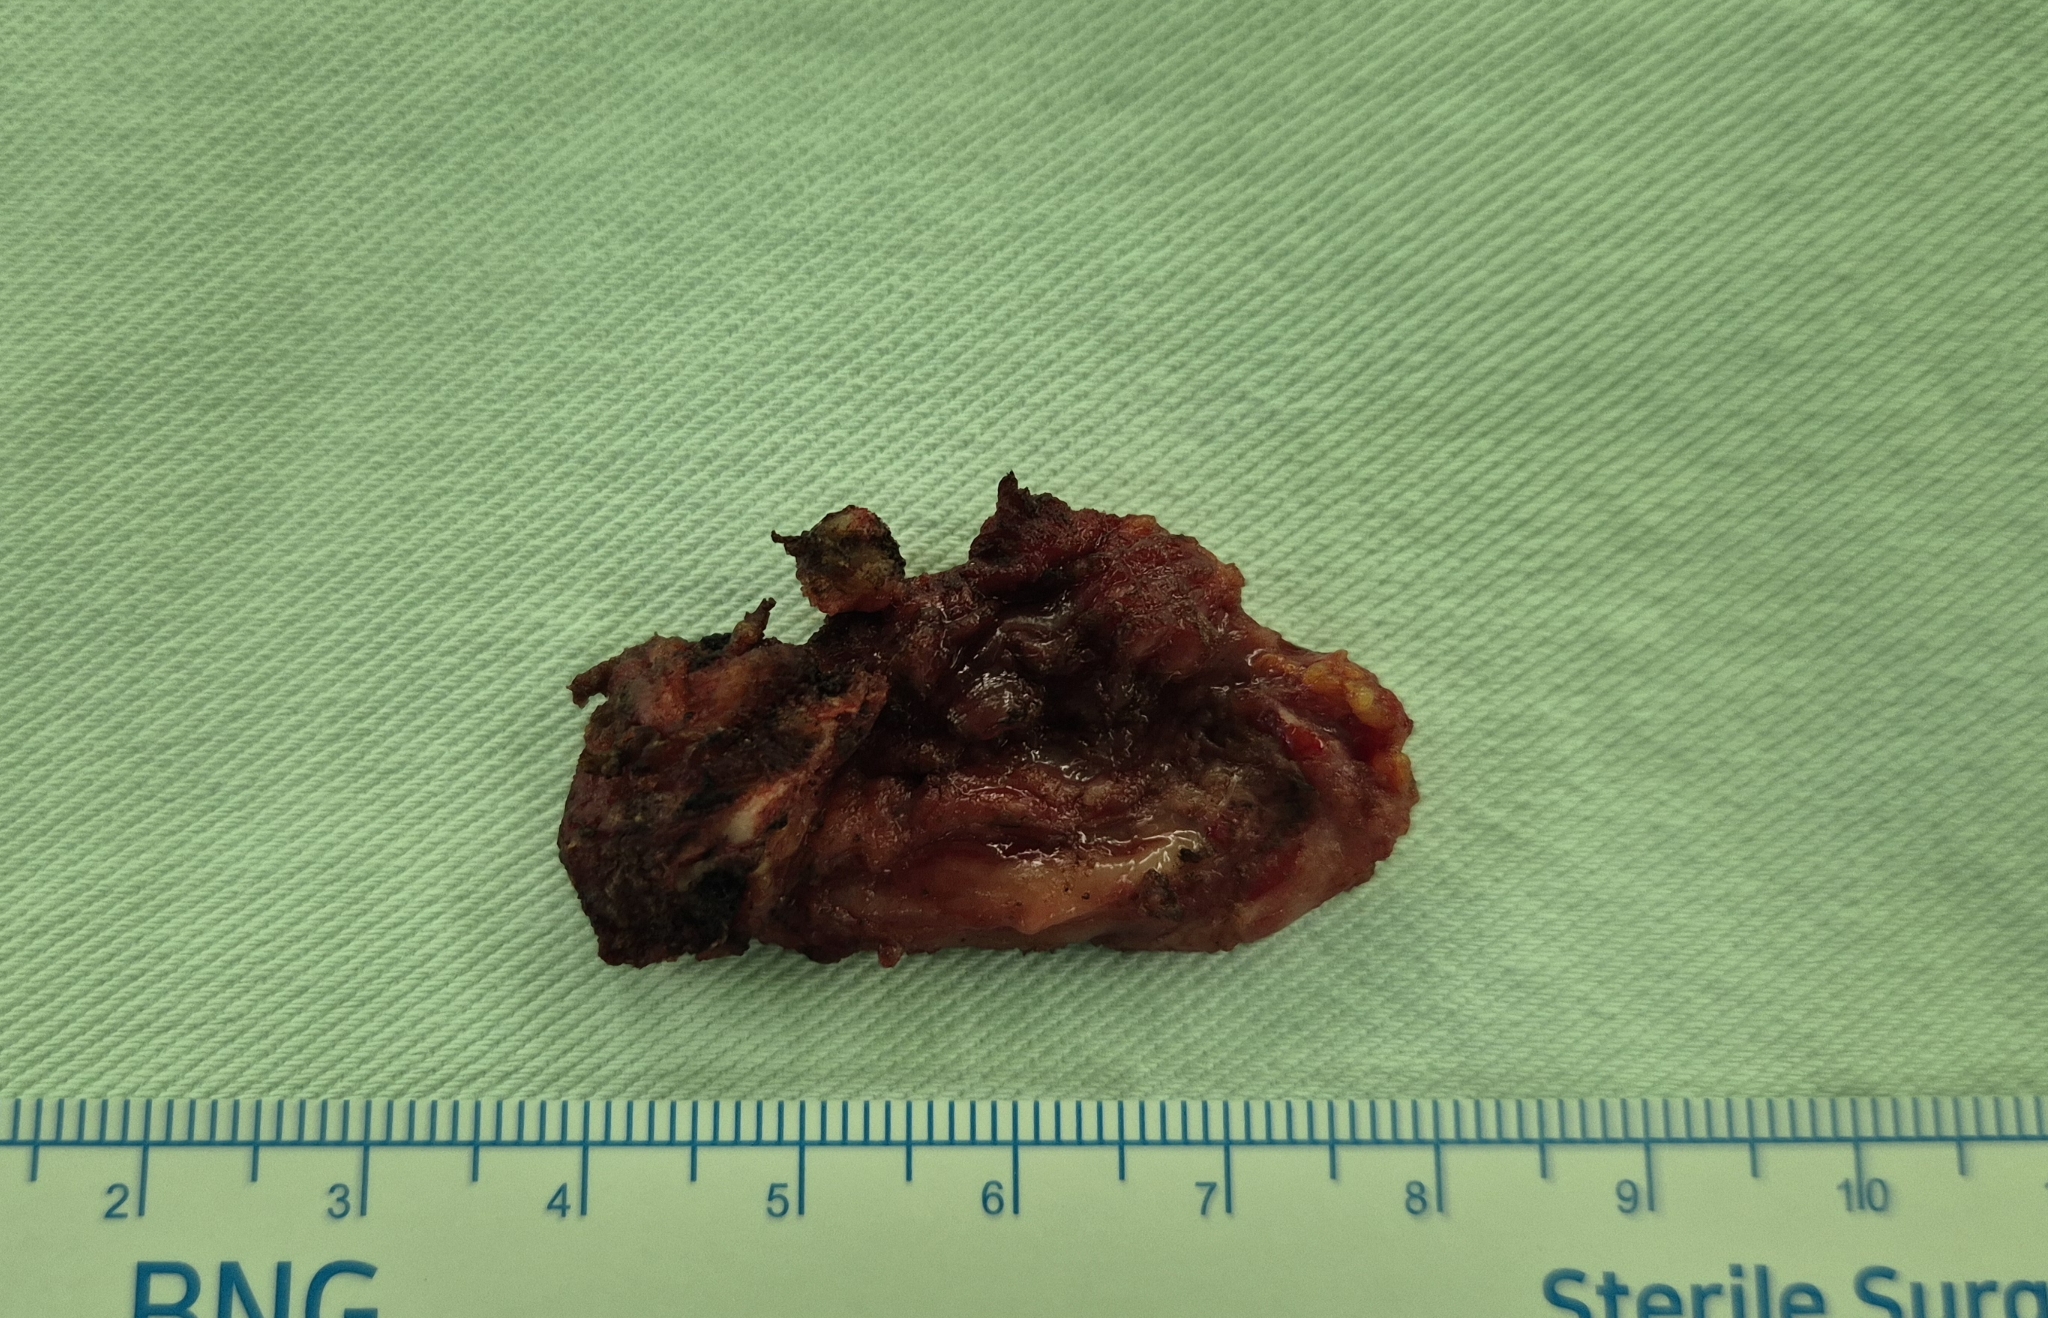

전경부 종물 주소로 내원하여 초음파 시행후 갑상선 설관 낭종으로 확인되어,

설골 부분절제 및 낭종절제술을 시행했습니다.